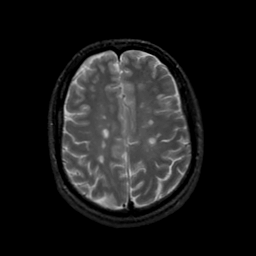

MR Study #22, December 1, 1991 -- Slice #36

[Home][Help][Clinical][Tour 1][Tour 2] Slice 36